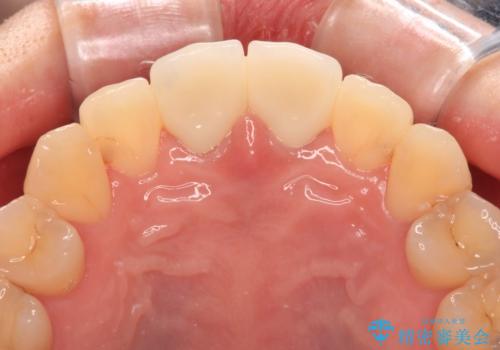

変色した前歯 オールセラミッククラウンにより審美歯科治療

- 神経を取り除いたことで経年変色した前歯2本を気にして来院された患者様です。

根管治療を行う必要はないと判断し、双方の歯にグラスファイバーを含有した土台を植立してオールセラミッククラウンにて補綴することとしました。

色調が周囲の歯とアウトともに、表面のつぎはぎや穴を封鎖した際の段差などが解消され、天然歯のような感触となりました。